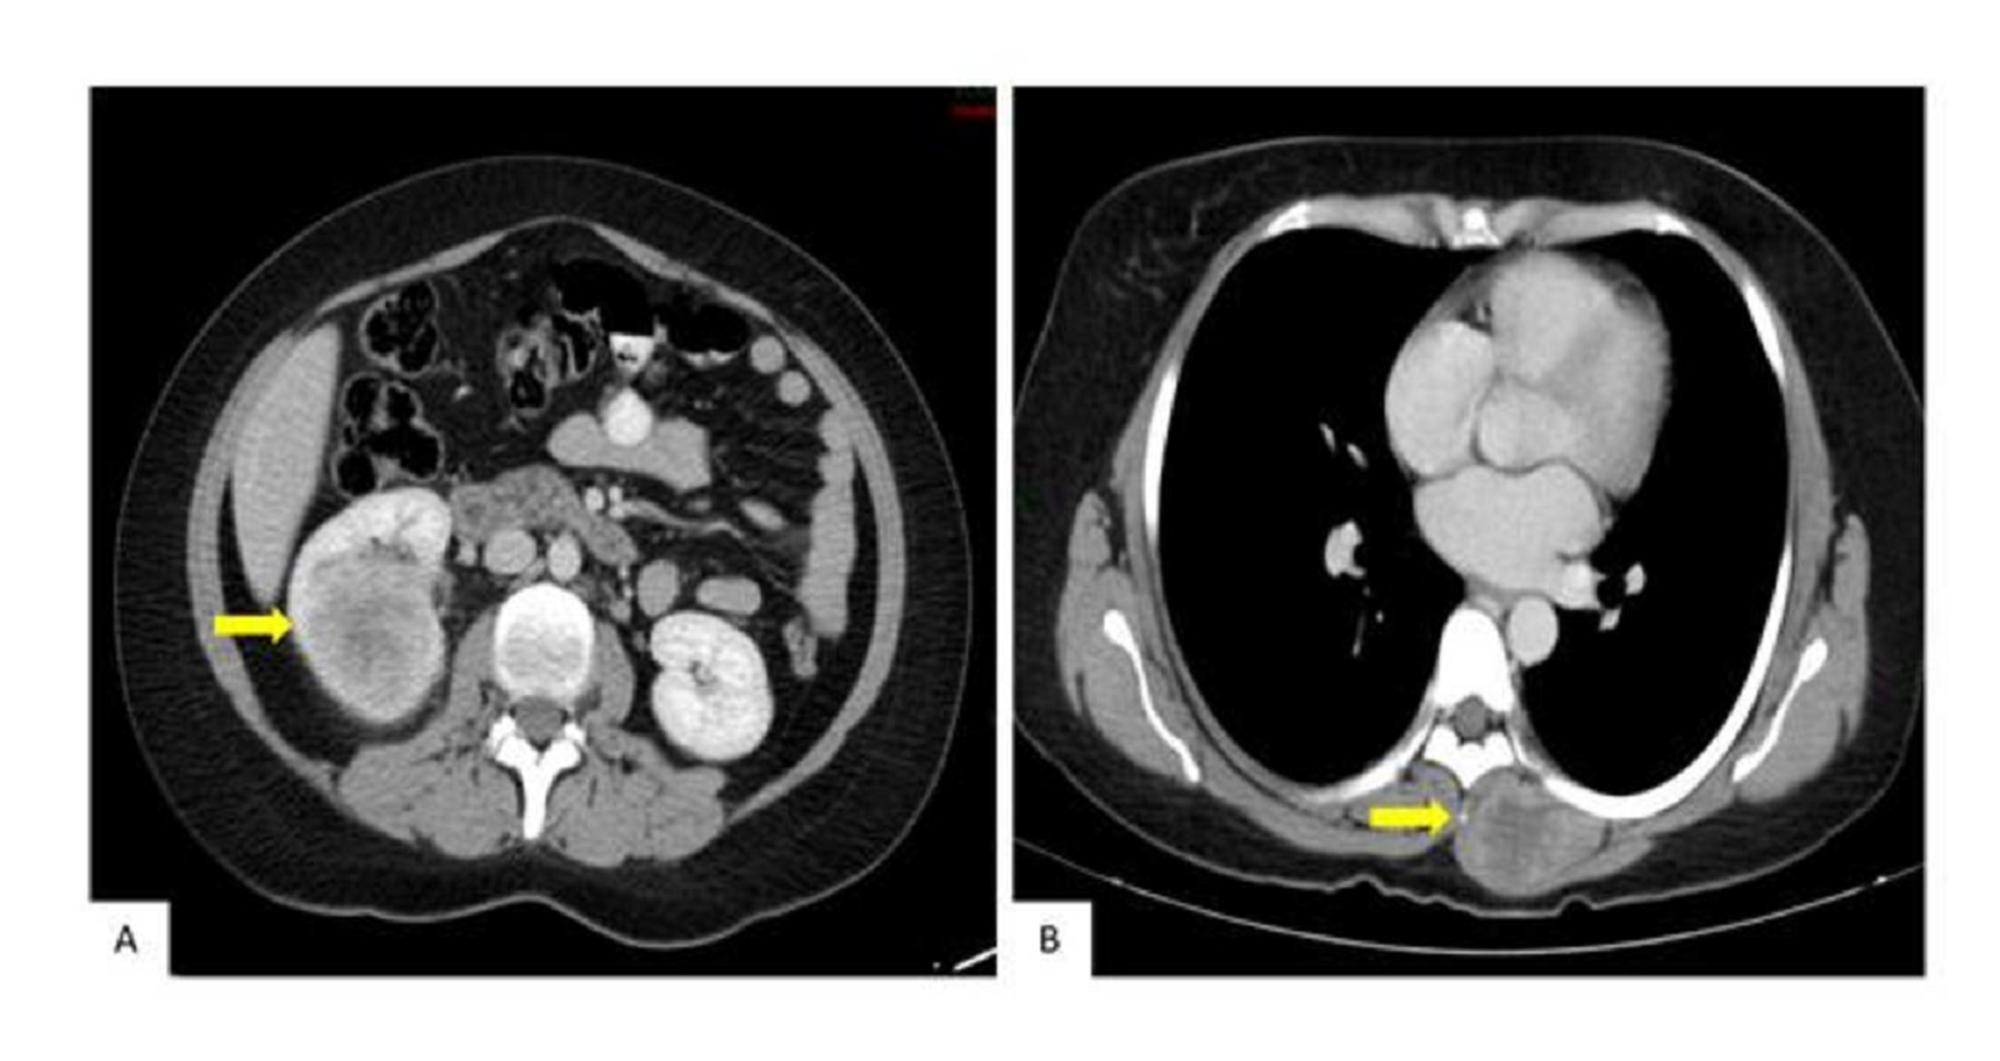

An abdominal and pelvic computed tomography (CT) scan showed a solid right renal lesion on the cortex of the middle third and lower pole of the right kidney measuring 4.9x5.1x5.2 cms (Figure 2A). A CT scan of the chest showed a solid lesion with peripheral uptake in the left paravertebral muscles at the level of T5-T8, measuring 3.8x2.8 cms in diameter (Figure 2B).

Abdominal and pelvic scans in January 2018 showed the progression of the tumor, disease in the right nephrectomy bed, and a new left renal lesion (Figure 5A). Magnetic resonance imaging (MRI) showed the persistence of the paraspinal lesion (Figure 5B). The clinically presented growth of the paraspinal mass was 15x11 cm. The patient declined further therapy and died of the disease in June 2018.